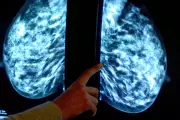

New breast cancer guidelines for dense tissue detection

Exclusive: New federal guidelines will help detect hard-to-find breast cancers in women with dense breast tissue, offering hope for earlier diagnosis and treatment.

New research reveals women with dense breast tissue face significantly higher cancer risks and poorer detection rates. Learn about this crucial health factor and what it means for your screening.